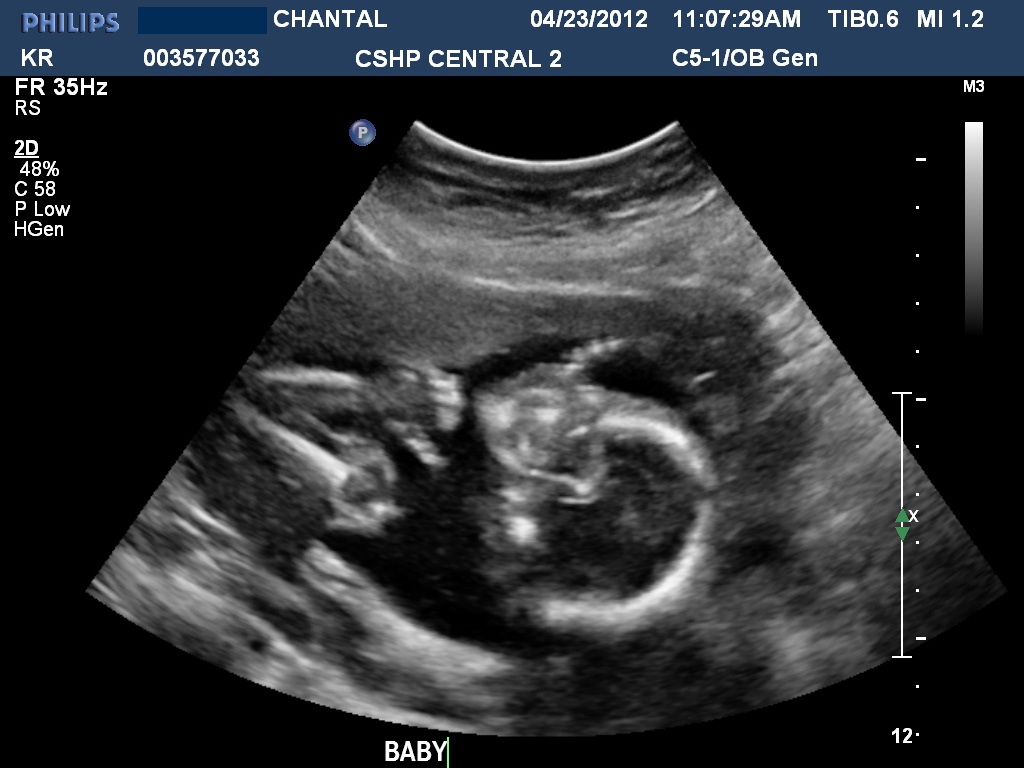

ANATOMY SCAN

Attachment 2237Attachment 2238